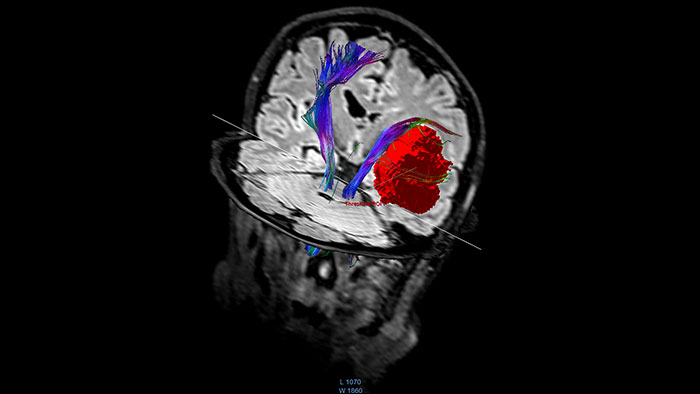

FiberTrak

MR FiberTrak

Visualize white matter connectivity in the brain

Provides visualization and quantification of white matter structure in the brain and spinal tracts using task guidance for generating common or user-defined tracts.

• The guidance panel suggests which regions of interest and plane are common for identification of certain tracts such as the corticospinal tract.

• The results can be overlaid with other data like fMRI or anatomical series.

• Allows evaluation of fiber tracts around tumors and lesions in combination with functional areas.

• Supports DICOM-based output with merged anatomical tractography information through the Multi Modality Viewer.